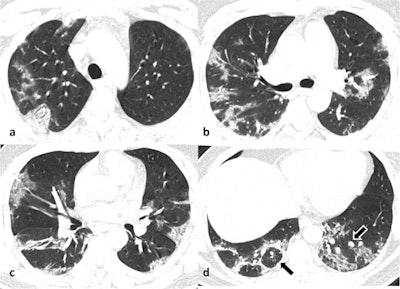

Lung parenchymal abnormalities were seen in 51 (35%) cases, whereas 96 (65%) cases with a positive reverse transcription polymerase chain reaction (RT-PCR) result had a normal chest CT. Only 12% of patients were dyspneic, 6% had desaturation, 7% had increased respiratory rate and 11% had comorbidities. Among the patients with abnormal CT findings, bilateral 39/51 (76.5%), multilobar (88%) lung involvement with a predominant peripheral and posterior distribution was commonly observed.

Ground-glass opacity (GGO) was the dominant abnormality found in all 51 cases. Pure GGO was observed in 15 (29%), GGO with crazy-paving pattern was seen in 15 (29%), and GGO mixed with consolidation was noted in 21(41%). Perilesional or intralesional segmental or subsegmental pulmonary vessel enlargement was observed in 36 (71%) of cases.